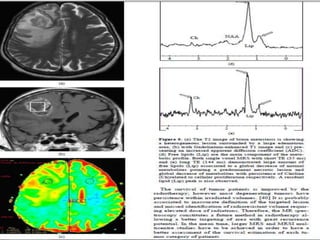

Patient with glioblastoma with oligodendroglioma component, WHO grade IV of IV.

(A) MRS spectrum from region of brain not affected by the tumor. (B) Spectrum from

a voxel within the tumor, showing elevated choline. (C) T1 MR image and (D) color-rendered

MRS image showing variations in the levels of choline within the tumor.